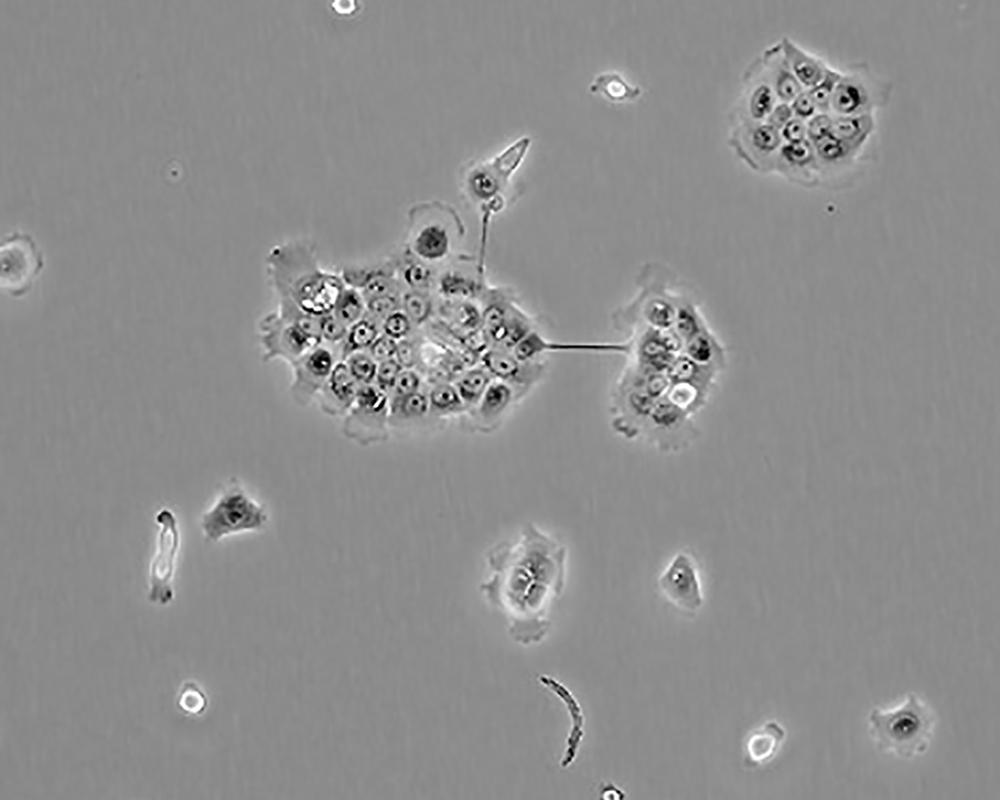

BxPC-3(BxPC3)

產品名稱 BxPC-3(BxPC3)

中文名稱 人原位胰腺腺癌細胞

組織來源 胰腺導管腺癌;女性

生長特性 adherent

形態特征 epithelial

細胞描述 The cells do not express the cystic fibrosis transmembrane conductance regulator(CFTR). A CFTR positive pancreatic line, Capan-1 is available.